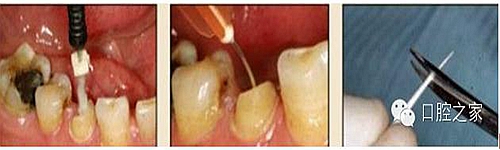

圖3:根管內(nèi)殘留物

圖4:超聲去除根管殘留物?! ?/p>

根管壁殘留物的存在直接影響著纖維樁的粘接和固位,是纖維樁脫落的主要原因之一。由于圓形的根管鉆和根管形態(tài)不完全一致,終鉆預(yù)備完成后大多情況下樁道側(cè)壁會有不同程度的牙膠和封閉劑等殘留物附著(圖 3)。因此,建議X線檢查根管預(yù)備情況,選用超聲潔牙機更換較細(xì)工作尖進(jìn)入根管,徹底去除樁道根管壁上附著的殘留物(圖4)。使用根管銼去除殘留物時,很難清除干凈;禁止使用牙膠溶劑如丁克除、氯仿等有機溶劑去除殘留物,以免破壞根尖區(qū)牙膠的封閉,或有機溶劑粘附于根管壁形成蠟?zāi)ざ绊懻辰印?#pages##